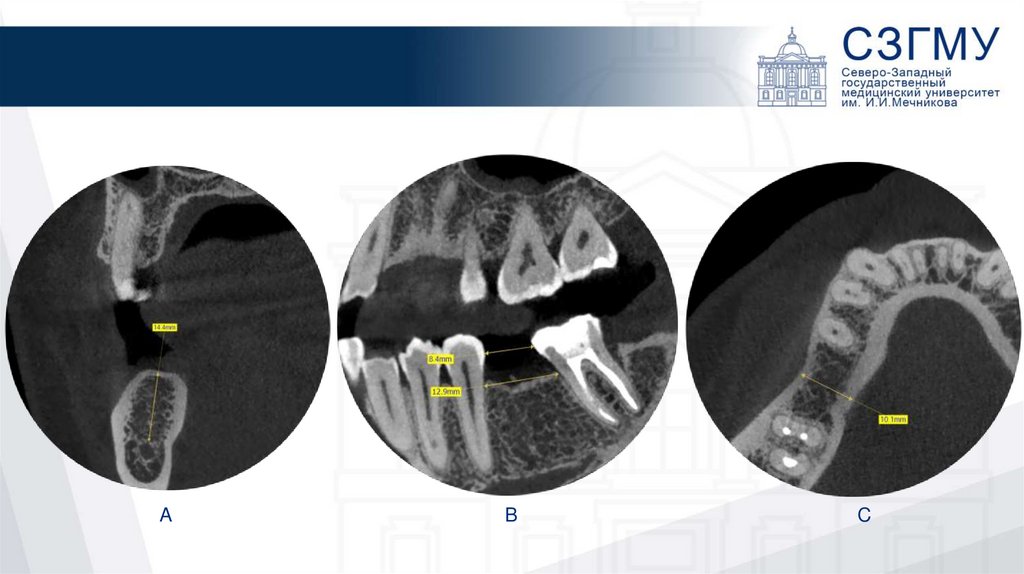

4.

A

B

C